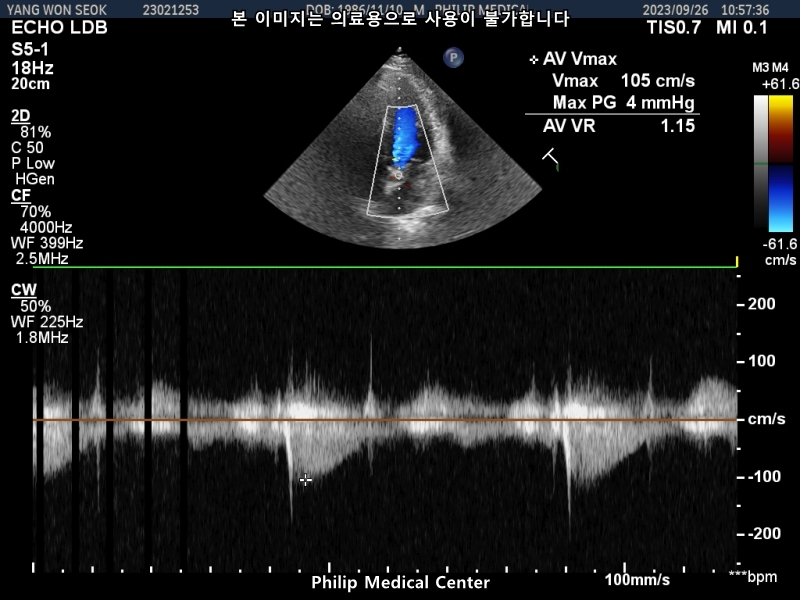

심장초음파는 경미한 폐동맥 판막역류소견과 심전도 검사결과 비특이적 ST-T파 이상소견이있었습니다.

결과지 첨부합니다,

• 1번 째 사진

• 2번 째 사진

• 3번 째 사진

• 4번 째 사진

• 5번 째 사진

• 6번 째 사진

• 7번 째 사진